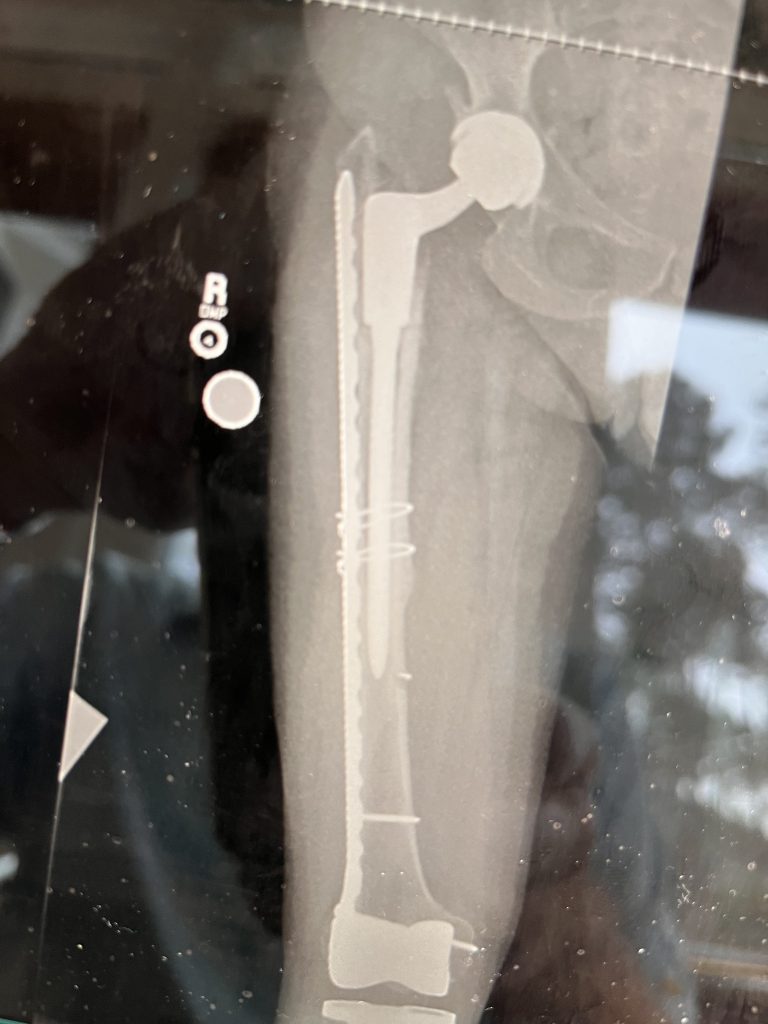

My story begins with being born with a severe case of bilateral coxa vara 73 years ago and having several osteotomies in my childhood years. These surgeries kept me mobile for six decades. By my mid-sixties, my hips were well past their expiration date and significantly slowing me down. After a few appointments with other orthopedic specialists who chose not to operate on me, I was referred to HSS and Dr. Robert Buly by a friend of the family. It couldn’t have turned out better for me. I have been a surgical patient of Dr Buly’s and HSS for the past 8 years. It is only through the dedication and the expertise of HSS and its staff and specifically Dr. Buly that I can walk for any length of time and put me Back in the Game. Thank you HSS, Dr. Buly, and his team.